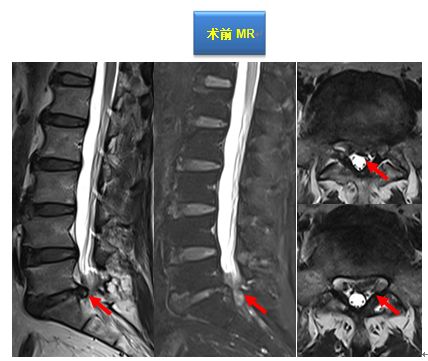

考虑诊断:1.脊髓型颈椎病(C3-6椎间盘突出并相应椎管狭窄) 2.颈背胸部肌筋膜综合征

其后按计划实施我院特色术式:改良精准微创式颈椎椎板成形术(该技术是在梁徳主任指导下由江晓兵副教授改良),手术按照标准化流程下进行,术中耗时60分钟,出血量约50 ml。术后复查如下:

术后MRI可见椎管内空间增大,脊髓后移退让,脊髓周围受压完全解除,术后患者双下肢乏力症状彻底消失。